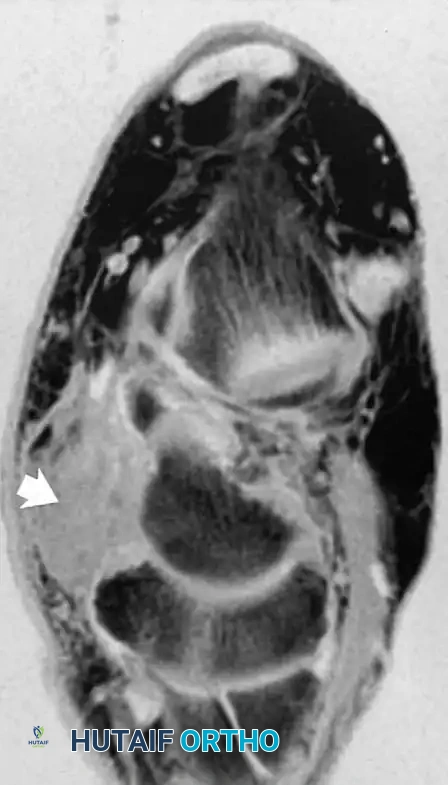

Fig. 2-4 Peroneus longus tendon rupture. A, Coronal T1-weighted image through midfoot shows increased diameter of peroneus longus tendon. B, Coronal fat-suppressed, T2-weighted image reveals fluid signal within ruptured tendon.